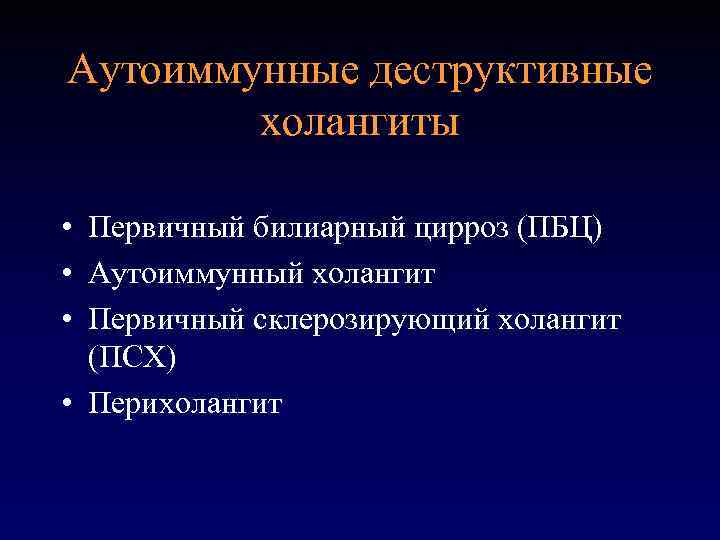

Фотографии и изображения, связанные с симптомами первичного склерозирующего холангита